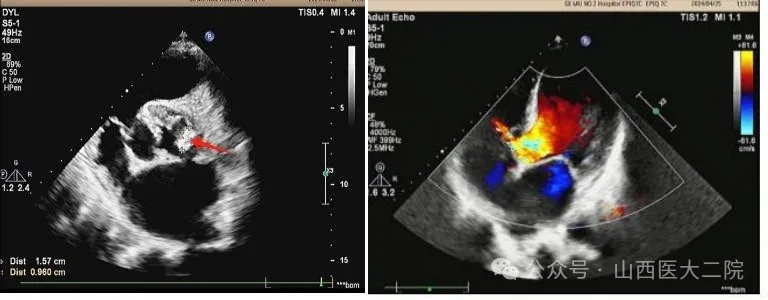

患者入院后行心脏彩超等辅助检查后诊断为:感染型心内膜炎、主动脉瓣赘生物,主动脉瓣二瓣化畸形伴重度关闭不全,二尖瓣中度关闭不全,室间隔缺损,肺动脉高压。布氏杆菌感染进一步加重了心功能衰竭。长期的心脏衰竭导致患者处于恶液质状态,体质瘦弱、骨瘦如柴、食欲低下、低蛋白血症,胸腔持续大量积液每日超过1000ml。心血管内科周荣副主任医师为其制定了精细的治疗方案,给予抗感染、利尿等多种措施治疗后,患者上述症状稍缓解,但须手术治疗方能彻底痊愈。

术后,患者入心胸外科重症监护室监护治疗。第二天,顺利拔除气管插管。第四天,转回普通病房。经过医护团队的不懈努力,以及患者和家属的积极配合,患者经受住了复杂心脏手术的风险,终获新生,体力、睡眠和食欲都恢复到正常人的水平,心脏恶液质得以逆转,即将痊愈出院。术后心脏超声显示,患者各瓣膜功能恢复良好。